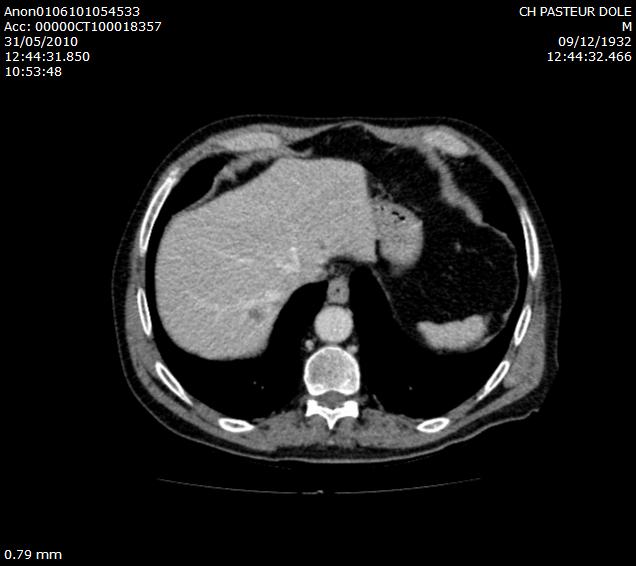

- Diffuse liver disease